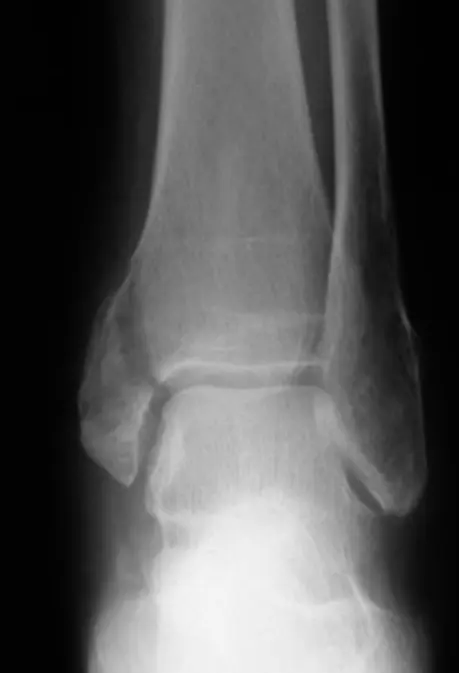

36âyearâold lady presents after a twisting ankle injury.

The ankle is swollen and tender, and she is unable to bear weight.

- Question: Is there a fracture?

- Likely site: possible lower fibula fracture

- Imaging needed: a lateral ankle film